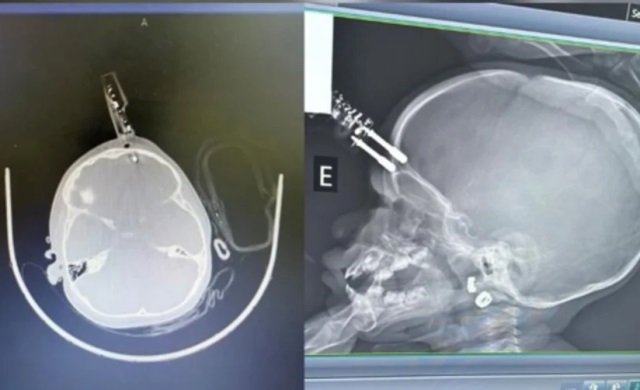

Uma menina de 1 ano precisou passar por cirurgia após cair da cama e ter um carregador de celular cravado na testa. O procedimento foi realizado na última terça-feira (13/1) em Divinópolis, no Centro-Oeste de Minas Gerais (MG).

A criança foi levada para a sala de cirurgia onde passou por procedimentos de limpeza, retirada do objeto, lavagem, fechamento e reconstrução da área atingida.